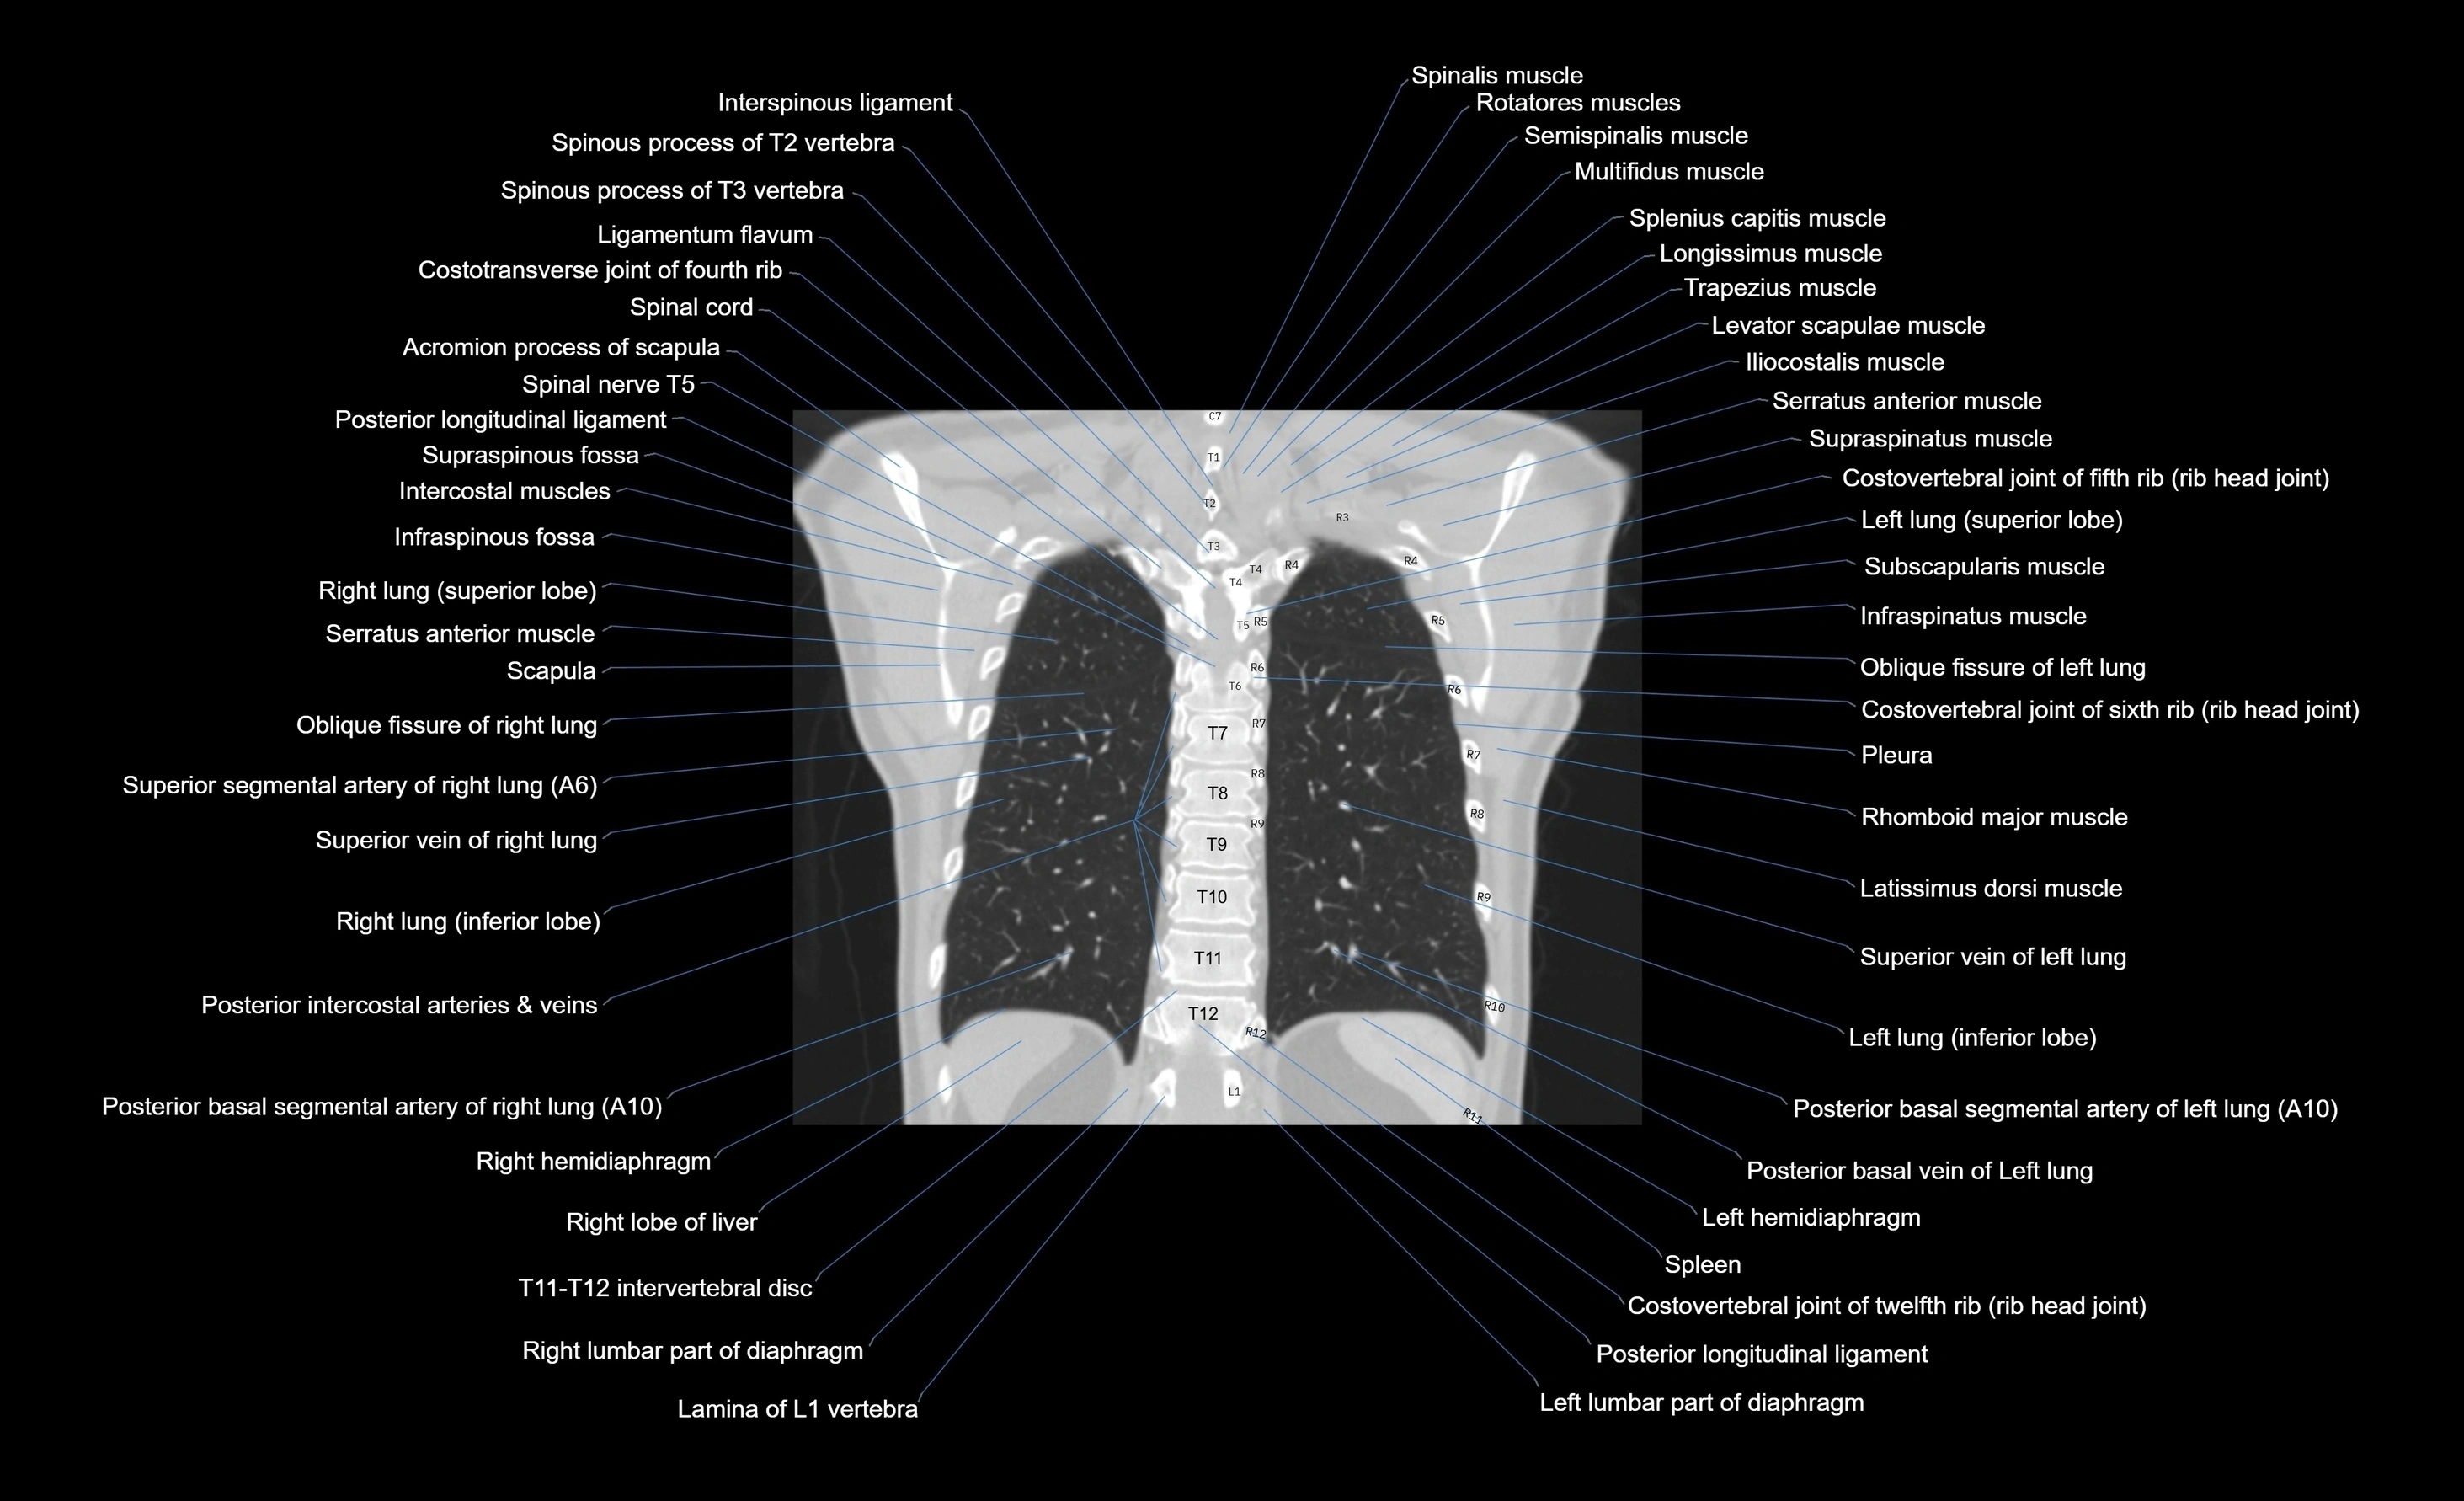

- T (Thoracic spine)

CT images